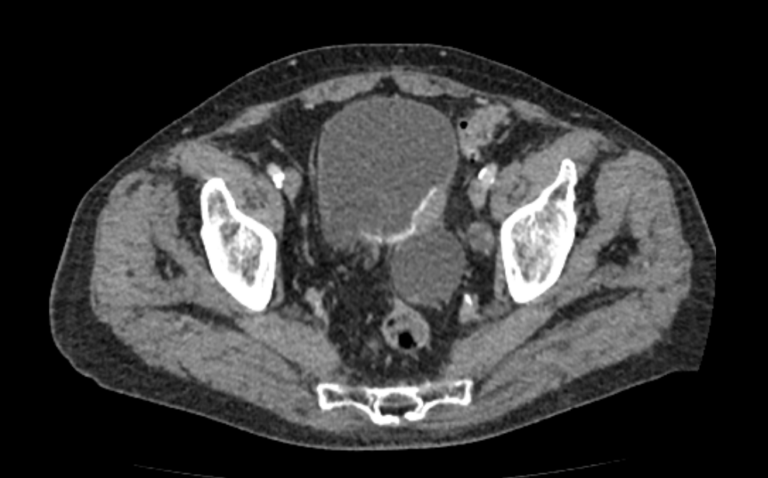

Мультиспиральная КТ мочевого пузыря является частью протокола обследования органов малого таза. Это высокоинформативный рентгенологический метод исследования, позволяющий детально визуализировать мочевой пузырь, нижнюю часть мочеточников, внутренние половые органы, прямую кишку.

Зачастую подобное исследование проводится при мочекаменной болезни (МКБ) для выявления конкрементов, определения их положения, размеров и плотности. Локализация конкремента существенно влияет на терапевтическое лечение МКБ, а наличие дивертикулов стенки мочевого пузыря на возможность самостоятельного выхода камня.

Также при данном исследовании возможно выявить утолщение стенки мочевого пузыря, что при диффузных изменениях может соответствовать проявлениям цистита, а локальные или неравномерные утолщения – характеризовать патологический процесс обусловленный новообразованиями.

Для улучшения визуализации патологических образований, в частности, при подозрении на опухолевый процесс, проводится внутривенное болюсное контрастирование. Методика контрастного усиления основана на введении в вену контрастного препарата, который в большей степени накапливается в патологически измененных участках и обеспечивает их яркую визуализацию на фоне здоровых тканей. Контрастирование дает возможность определить врачу границы опухоли, оценить степень прорастания в соседние органы и ткани, выявить опухоли минимальных размеров (как первичного, так и метастатического характера).

Что позволяет увидеть КТ мочевого пузыря

- цистит;

- дивертикулы мочевого пузыря

- цистоцеле

- уретероцеле

- варианты строения мочеточников

- камни мочевого пузыря;

- травмы, разрывы и растяжения органа;

- опухолевые новообразования.